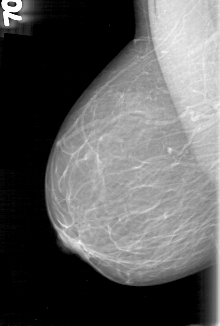

D_4060_1.RIGHT_CC

RIGHT_CC LINES 5281 PIXELS_PER_LINE 3091 BITS_PER_PIXEL 12 RESOLUTION 43.5 NON_OVERLAY